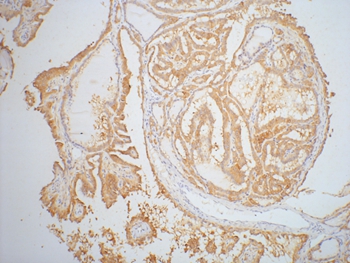

图片:

IHC staining of paraffin-embedded Human thyroid tissue with Galectin-3 mouse mAb£¨6G2£?diluted at 1:200.